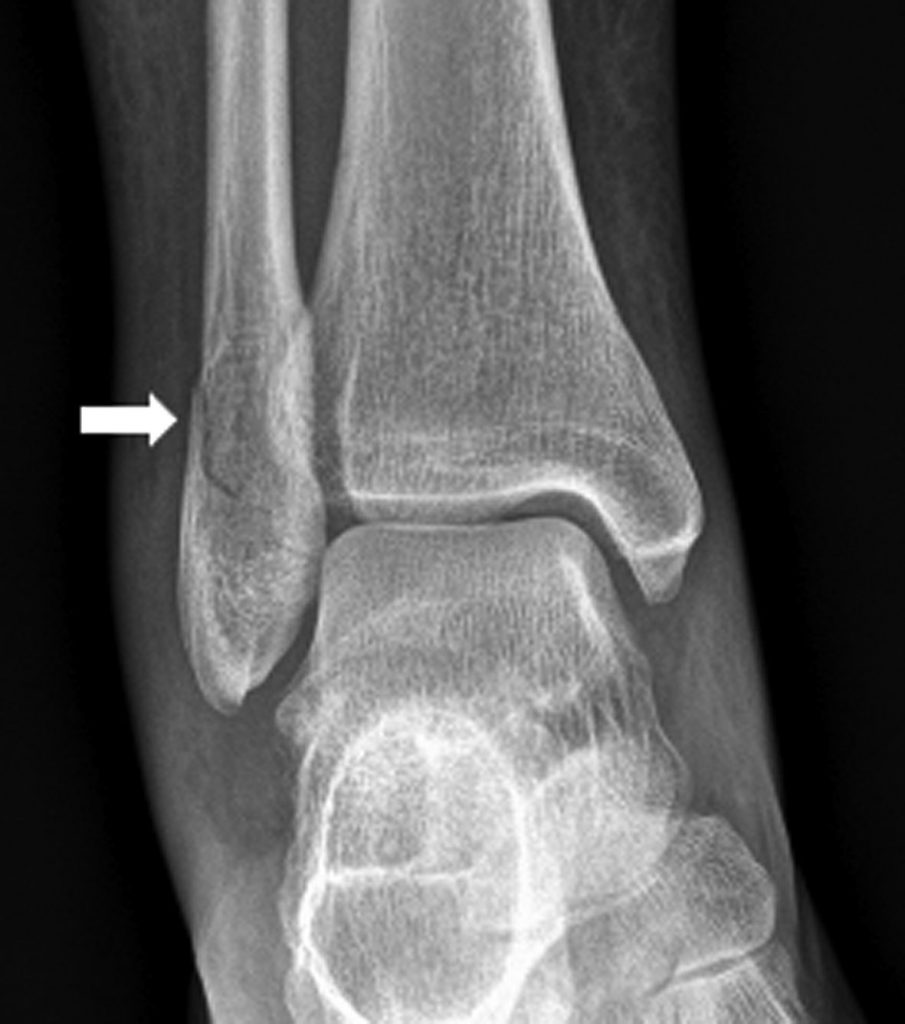

En cas d’entorse simple (lésion ligamentaire pure), les radiographies sont normales ou peuvent montrer un épaississement des parties molles en regard du ligament atteint (figures 79.3). Une avulsion osseuse de l’enthèse ligamentaire sur le site d’insertion du ligament peut être visible (figure 79.4).

Fig. 79.4 Entorse de cheville.

Radiographie de cheville de face montrant une avulsion osseuse de l’enthèse fibulaire du ligament collatéral latéral.

Source : CERF, CNEBMN, 2022.